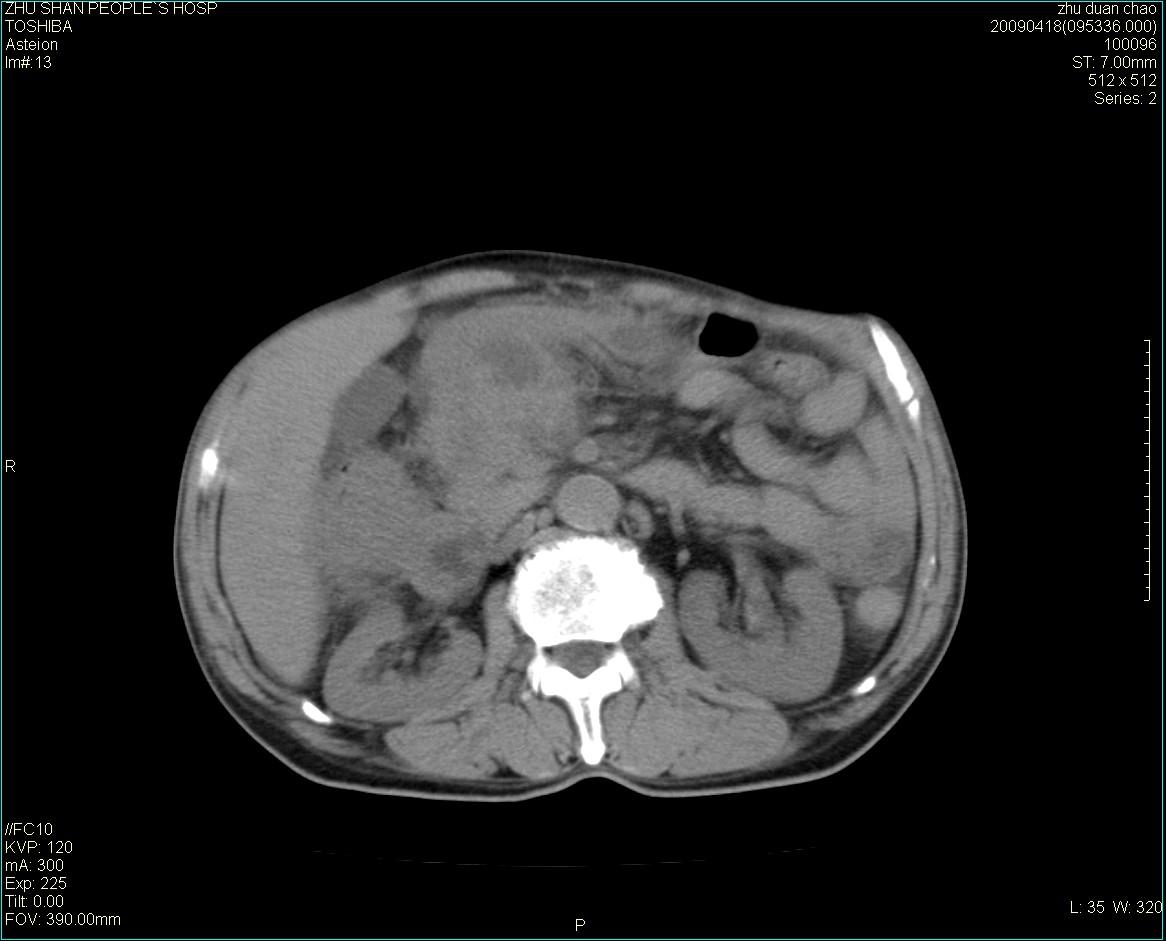

以下是引用余辉在2009-4-22 10:48:00的发言:[br]结肠肝曲附近肠段包块,病灶密度不均匀,周围肠系膜脂肪混浊,见多枚淋巴结肿大,考虑结肠癌可能性大,病灶累及范围较广建议进一步检查除外其他

以下是引用随光逐影在2009-4-22 11:57:00的发言:[br]考虑肠道肿瘤(间质瘤?)可能性大。

以下是引用ydx_74在2009-4-22 14:39:00的发言:[br]结肠癌周围侵犯可能,不能完全除外炎性病变